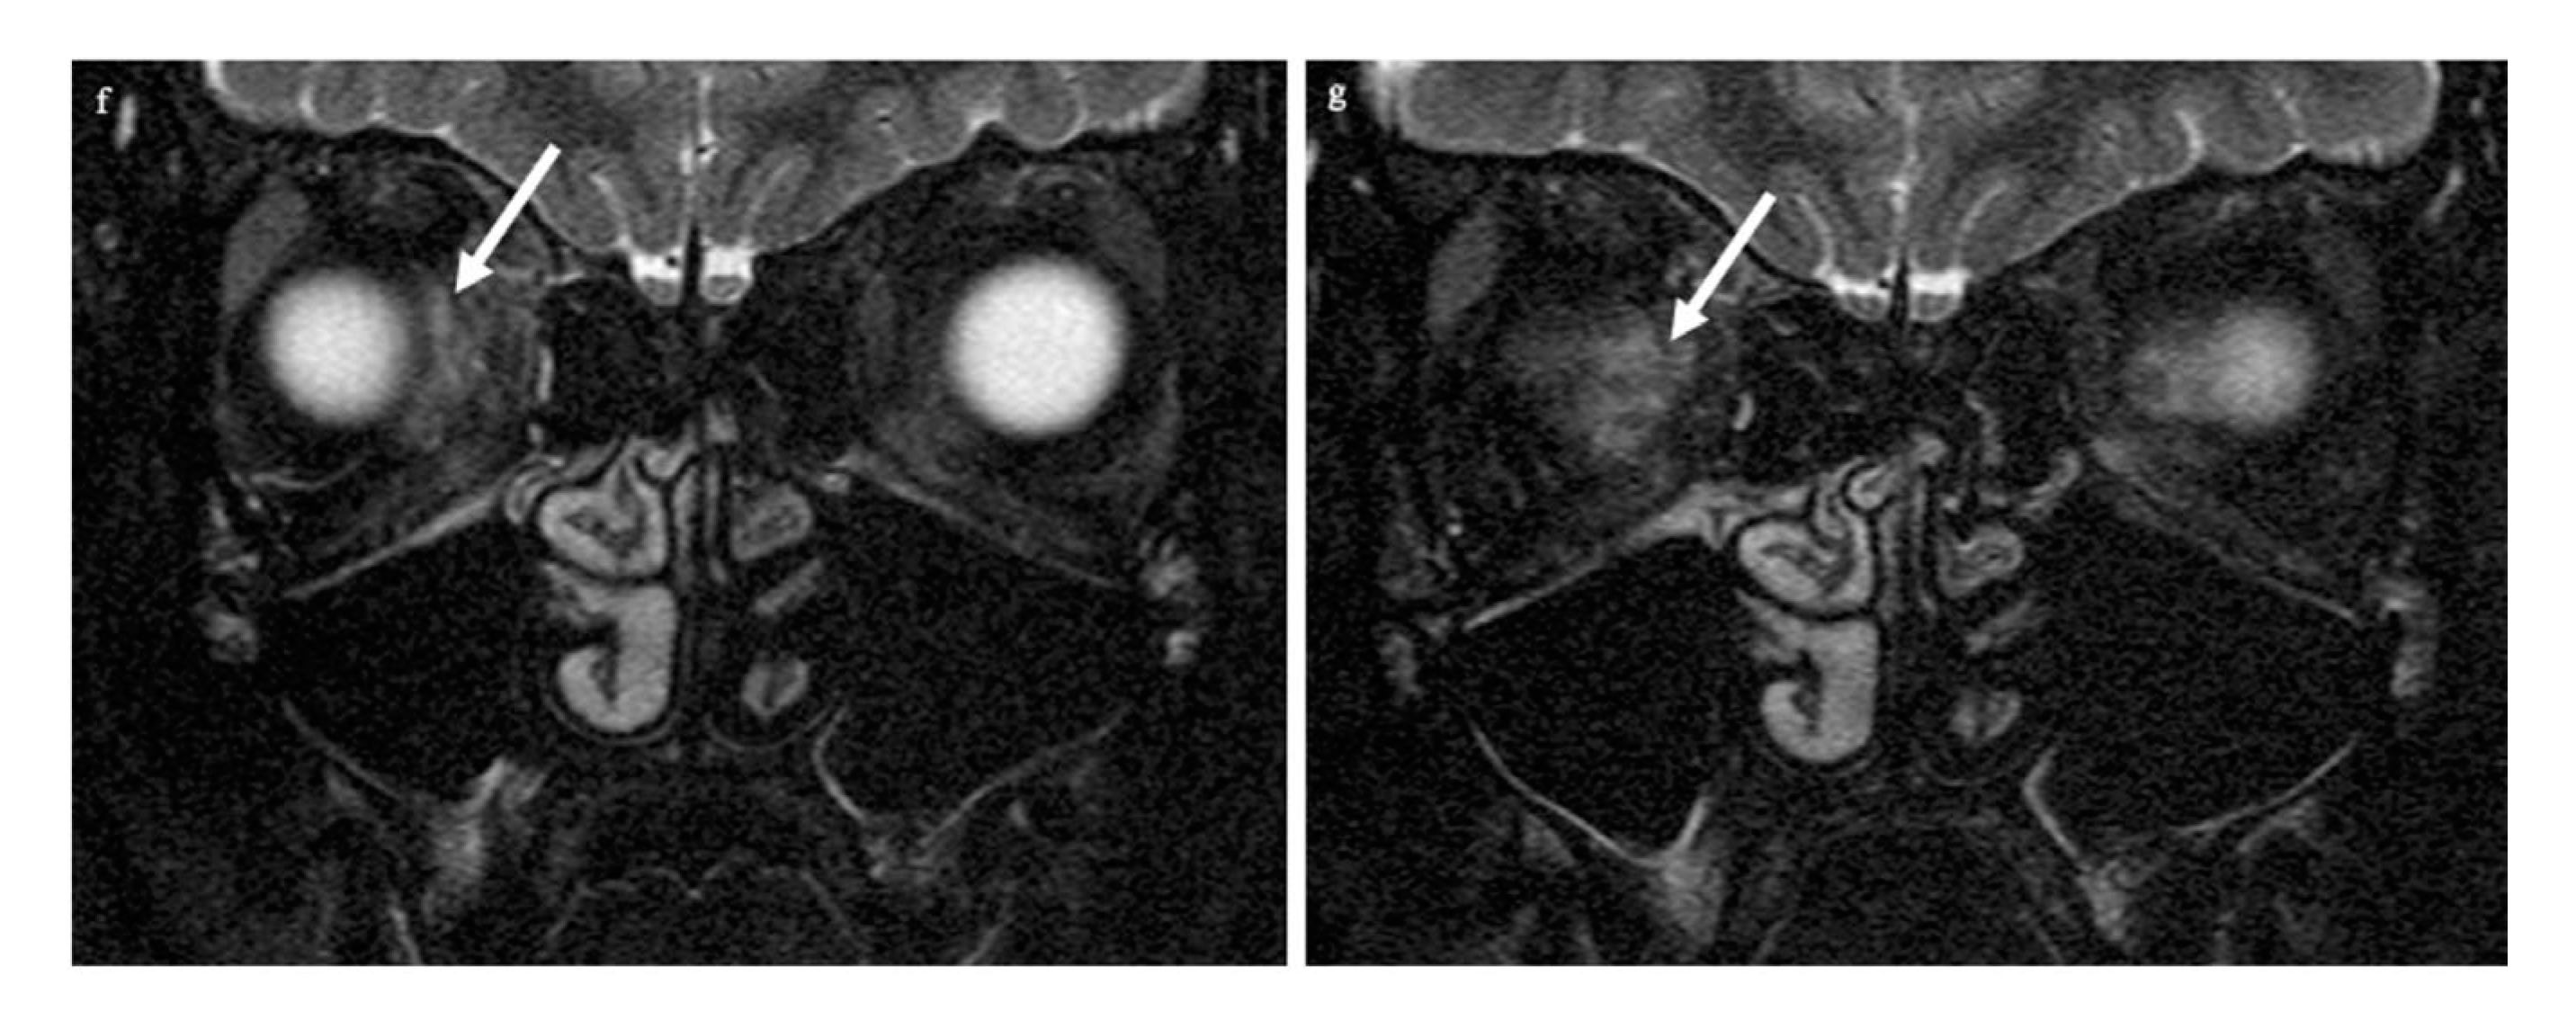

Examination of the right eye revealed a superficial conjunctival wound nasally and a dilated pupil (a). On the MRI scan, there is loss of the subarachnoid space in the right optic nerve (arrows in panel (b): the subarachnoid space of the left optic nerve is normal). The respective transverse T2-weighted image shows a central signal increase in the optic nerve (arrow in (c)). On the diffusion-weighted imaging, a punctuate signal increase in the optic nerve in the same location is seen (arrow in (d)); the corresponding ADC map shows signal loss in the same location (arrow in (e)). The globe as well as the left eye and orbit are unchanged, while there is a diffuse signal increase (arrows) in the right retrobulbar space nasally (f,g).

CT of the facial skull showed neither fractures nor foreign bodies, metallic or otherwise (Somatom Excite, Siemens Healthineers, Erlangen, Germany). The optic canal was normal. MR imaging was performed 4 hours after the trauma on a 1.5 T imager (Symphony, Siemens Healthineers, Erlangen, Germany) with a standard head coil. Plain T1w spin-echo images in the transverse orientation (TR 500 ms, TE 8.8 ms) and plain T2w turbo spin-echo transverse and coronal images with and without fat saturation (TR 4.000 ms and TE 128 ms) by prepulse were obtained in a 2 mm slice thickness. For DWI and ADC maps, a transverse orientation was chosen (5 mm slice thickness, TR 2500, TE 80 ms, and b-value of 1.000 s/mm2). Imaging demonstrated on coronary T2-weighted fat-saturated MRI loss of the subarachnoid space in the right optic nerve (white arrows in panel b: the subarachnoid space of the left optic nerve is normal) while the respective transverse T2-weighted image revealed slight optic nerve distention with a central signal increase (white arrow in c) right frontally from the optic canal. Diffusion-weighted imaging showed a punctuate signal increase in the optic nerve in the same location (d); the corresponding ADC map had signal loss in the same location (e). The globe was unchanged, while the retrobulbar space showed a diffuse signal increase nasally (f,g). The left eye and orbit were normal.